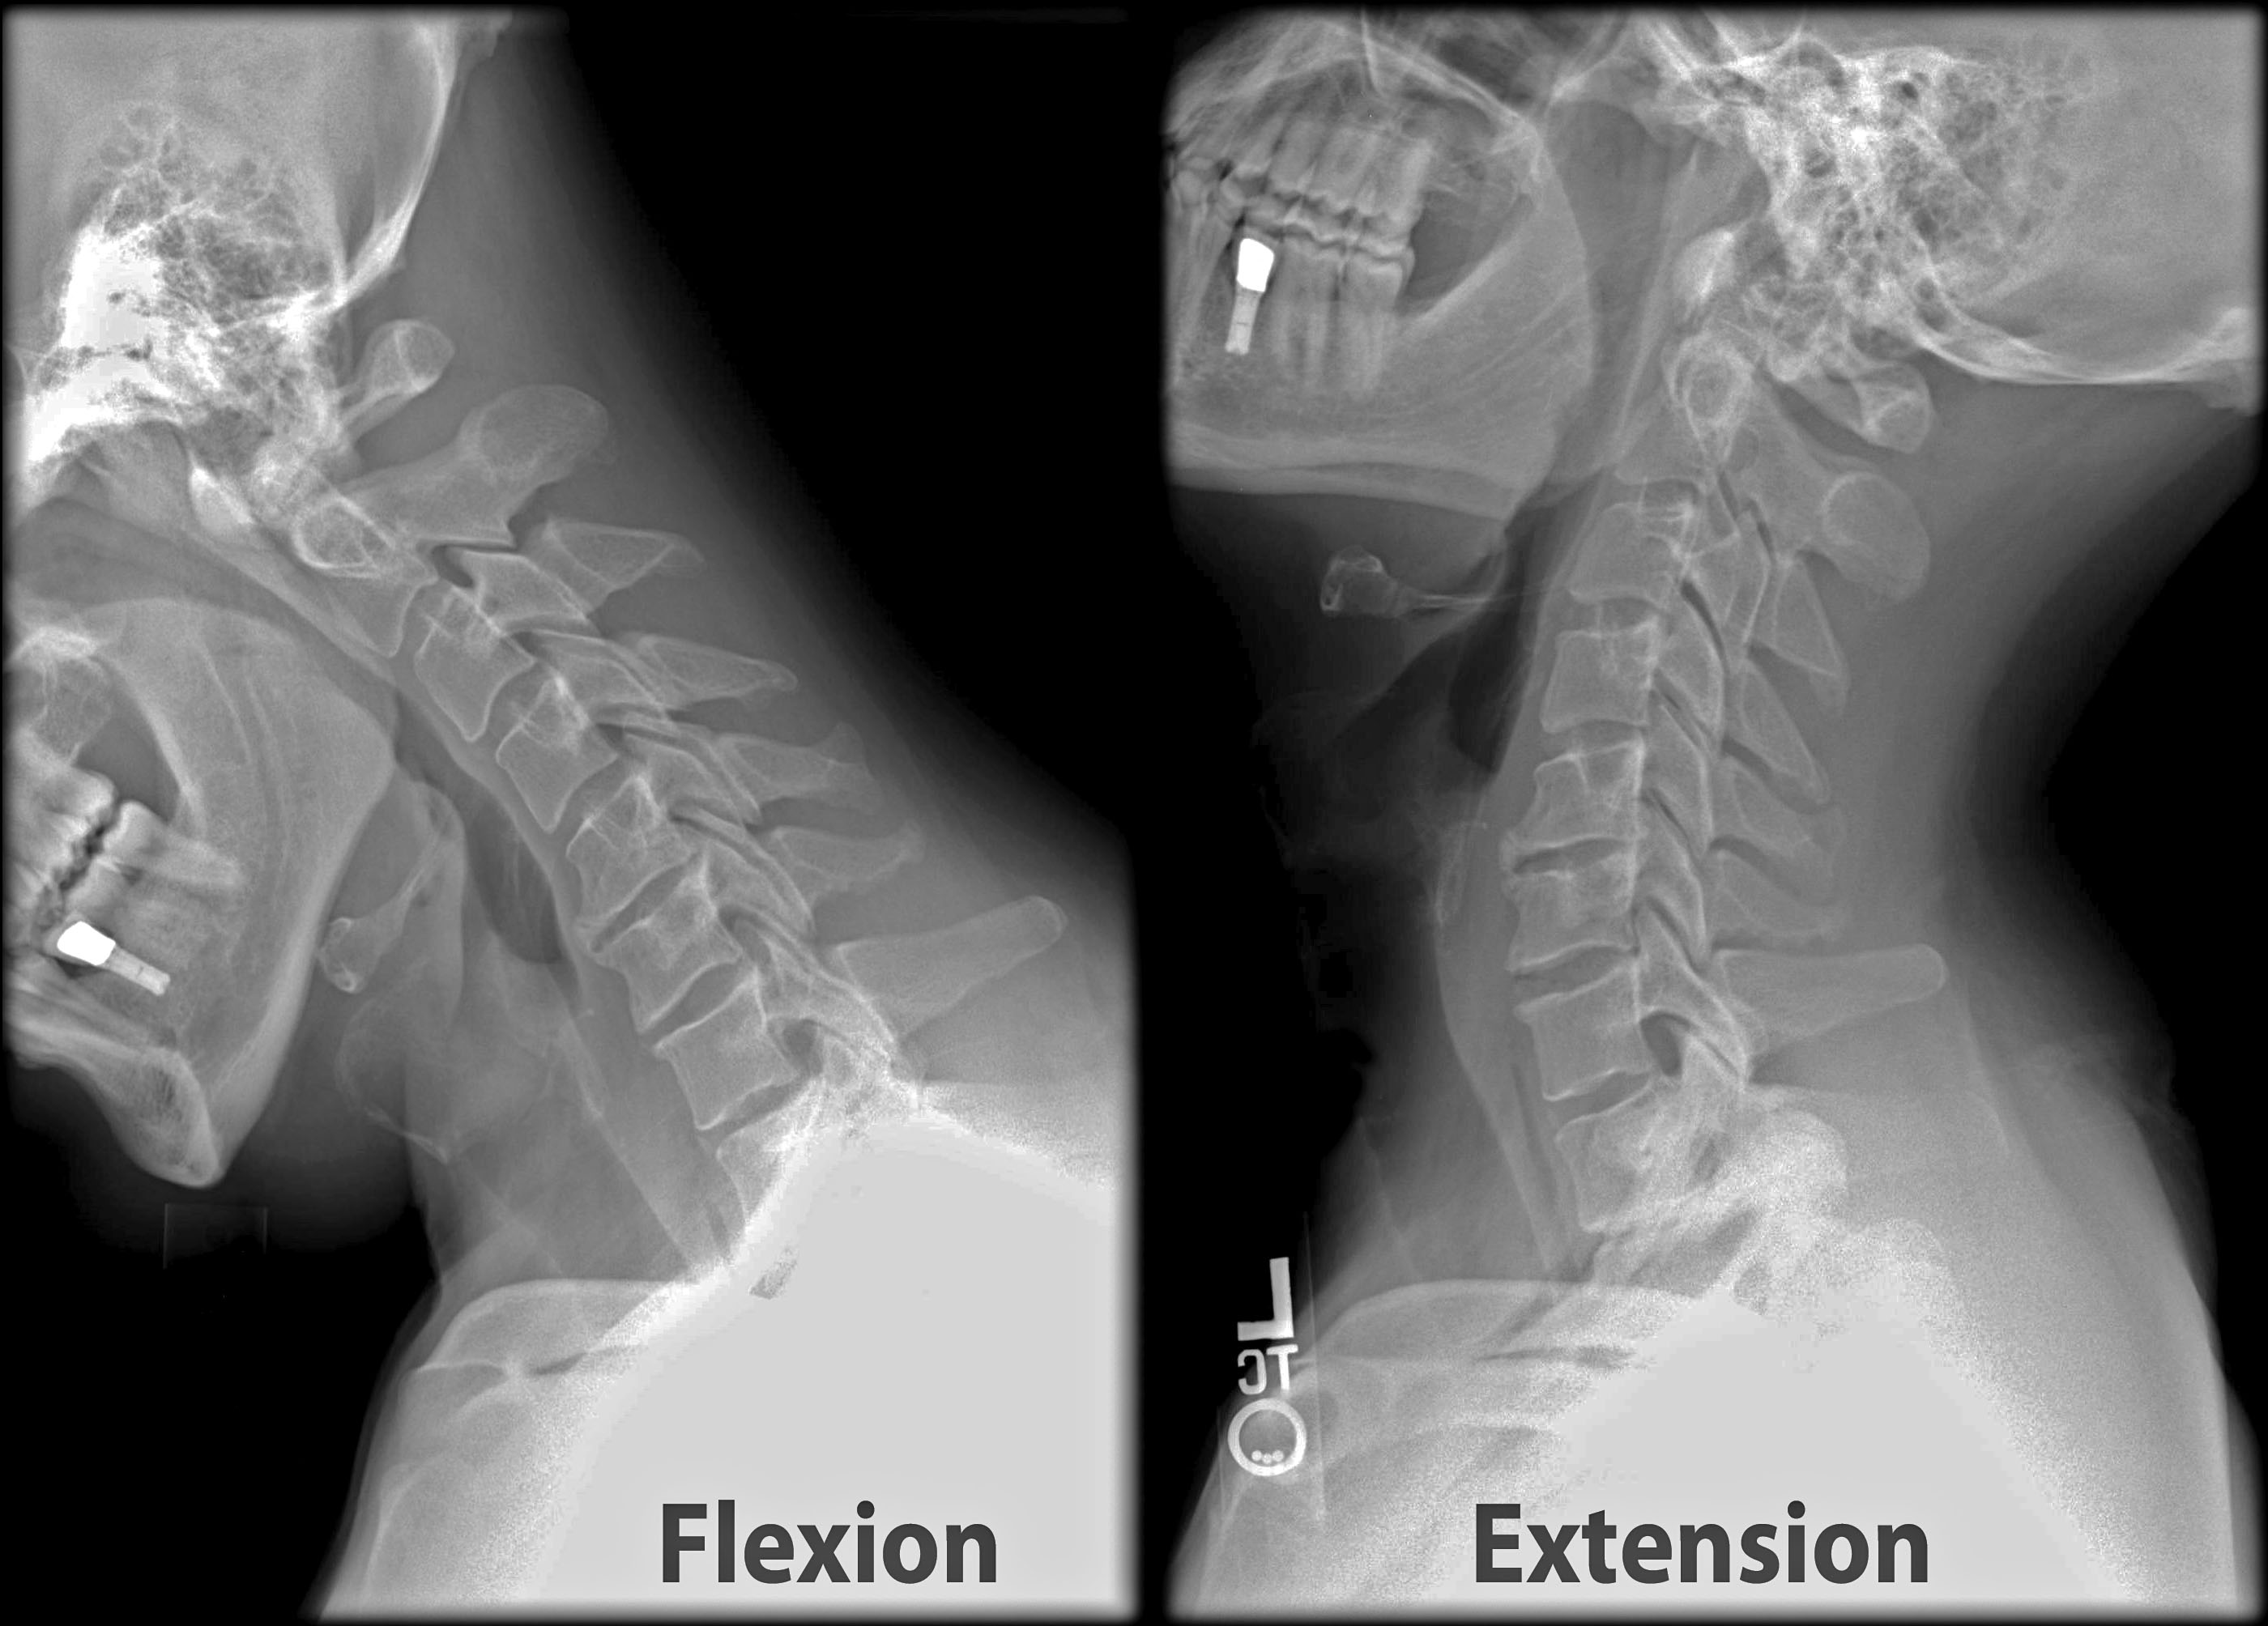

특히 청소년·대학생은 근골격계가 완전히 발달하지 않았기 때문에, 장시간 전방머리자세가 경추의 곡률(Cervical Lordosis)을 무너뜨리고 조기 퇴행성 변화를 불러옵니다.

좁은 좌석, 전방 주시 자세, 차량 진동은 모두 **두개-척추각(CVA, Craniovertebral Angle)**을 줄여 거북목을 심화시키는 요인입니다.

한 신경외과 교수는 “CVA가 작을수록 현훈 지수(DHI)가 높아지고, 경추 고유수용성 오류(JPE)가 증가한다”며, 목이 앞으로 나가면 단순 통증이 아니라 균형감각과 신경계 정확성까지 무너진다고 설명합니다.